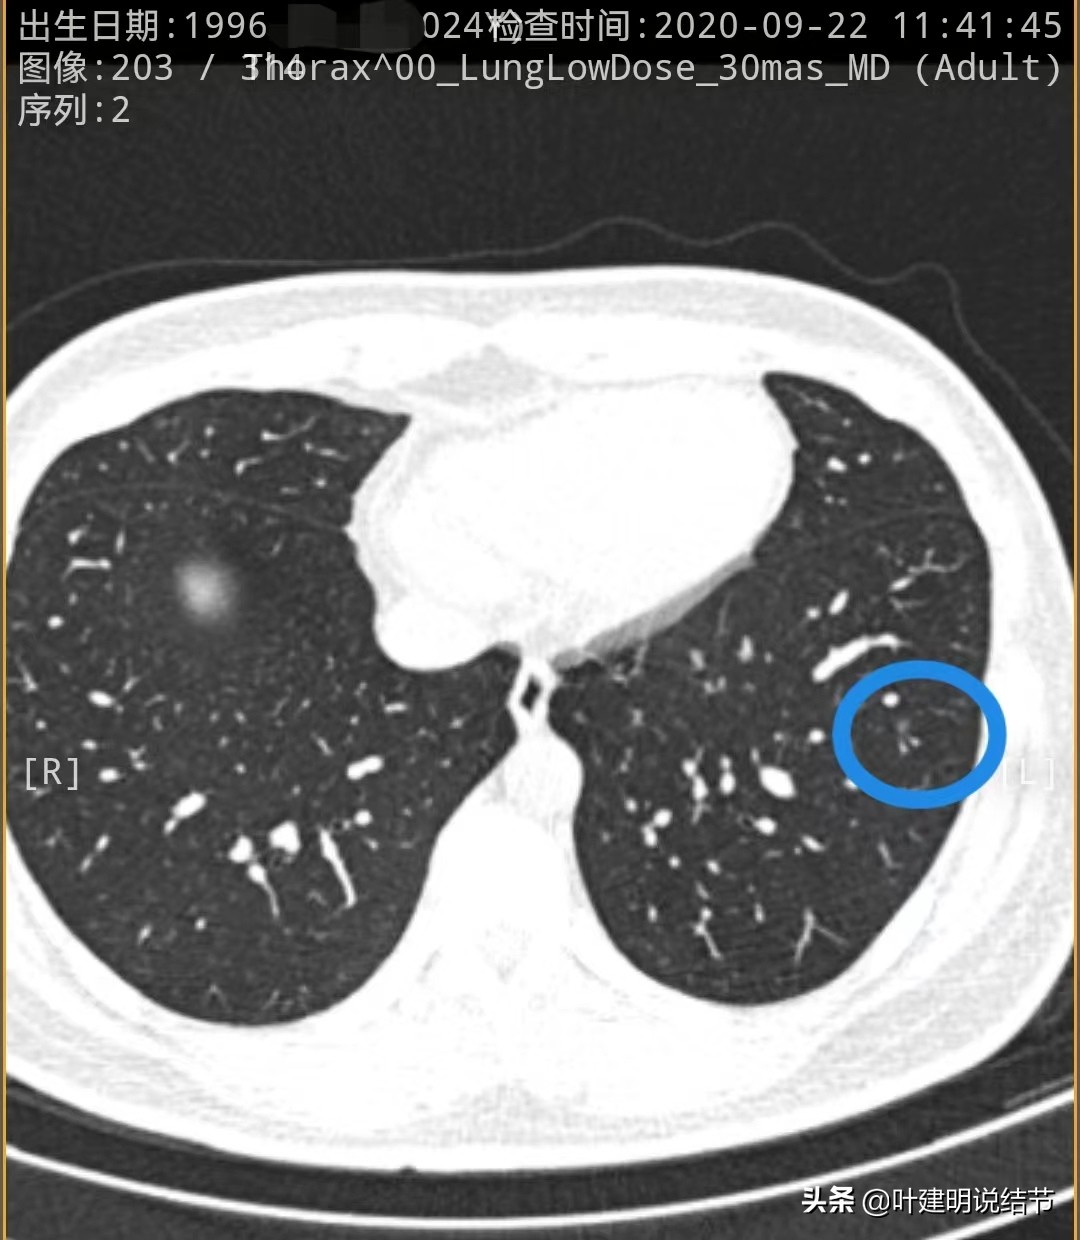

先来看2020年时的CT图像:

左下叶淡磨玻璃结节,轮廓较清,没有实性成分,以不典型增生可能性为大些

左下叶另一结节,密度低,轮廓 也清,考虑腺体胶驱病变,不典型增生或原位癌可能性大些